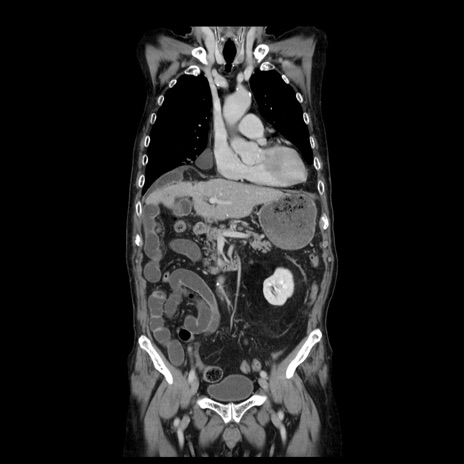

症例21(冠状断像)

【症例】70歳代男性

【主訴】腹痛

【現病歴】肝硬変・肝細胞癌にてかかりつけの方。約9時間前に食後より腹痛出現。症状が徐々に増悪し、嘔吐出現したため来院。

【既往歴】肝硬変、肝細胞癌(RFA、TACE後)

【身体所見】意識清明、表情苦悶様、BT 36℃、BP 129/78mmHg、P 88bpm、SpO2 97%(RA)、右上腹部から心窩部にかけて圧痛あり、反跳痛なし、筋性防御あり。

【データ】WBC 5800、CRP 0.16